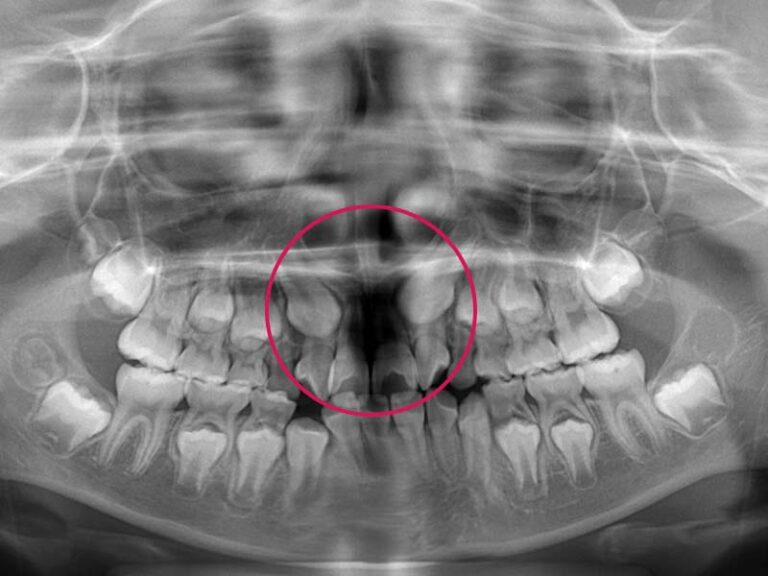

埋伏歯に多いのが、糸切り歯(犬歯)が生えてこないケースです。埋伏している犬歯の方向が、横を向いていることで、骨の中で他の歯の根っこと当たってしまっていることがあります。そのように歯に当たっていると、周りの歯の根っこが吸収して短くなってしまうことがあります。他の歯への影響が考えられる場合には、なるべく早く治療を行う必要があります。